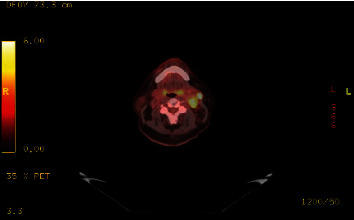

Paragangliomas are rare neuroendocrine tumors that arise from the paraganglia, which are clusters of neuroendocrine cells associated with the autonomic nervous system. These tumors are commonly found in the adrenal medulla but can also occur in other locations outside the adrenal gland. Here, we present a case report of a slow-growing paraganglioma in the left neck with spinal metastasis in a 60-year-old man. This case highlights the importance of considering paraganglion tumors in the differential diagnosis of neck masses and the need for early diagnosis and management to prevent potential complications. Importantly, both the clinical picture and anatomical location of these tumors is important when determining treatment plans.